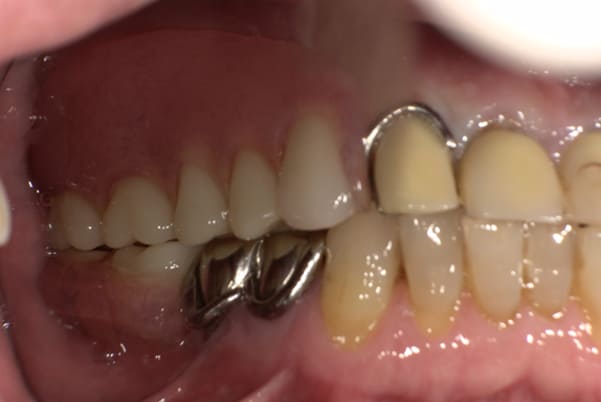

入れ歯が沈み込むことを防止するストッパーがない入れ歯を装着されていたため、お食事により入れ歯が沈み込みお痛みがでている状態でした。

笑った際に、太いバネが左右に見えるため、あまり大きく笑うことを避けていらっしゃいました。

作製した入れ歯は、お食事の際に入れ歯の沈み込みを予防するため、適切なストッパーを付与することで、入れ歯は沈み込まなくなり、お痛みは消失しました。

右下のバネの位置は後ろに、左下のバネは見えづらい形態のバネを用いる設計とすることで笑った際にバネが見えないようになり、気にされることはなくなられました。

裏側の見えない部分は金属を用いることで、お食事の際の入れ歯の動き、沈み込みを抑えお痛みがでづらく、入れ歯の動きが抑制されることで、長期的に残りの歯に負担のかかりにくい設計としました。